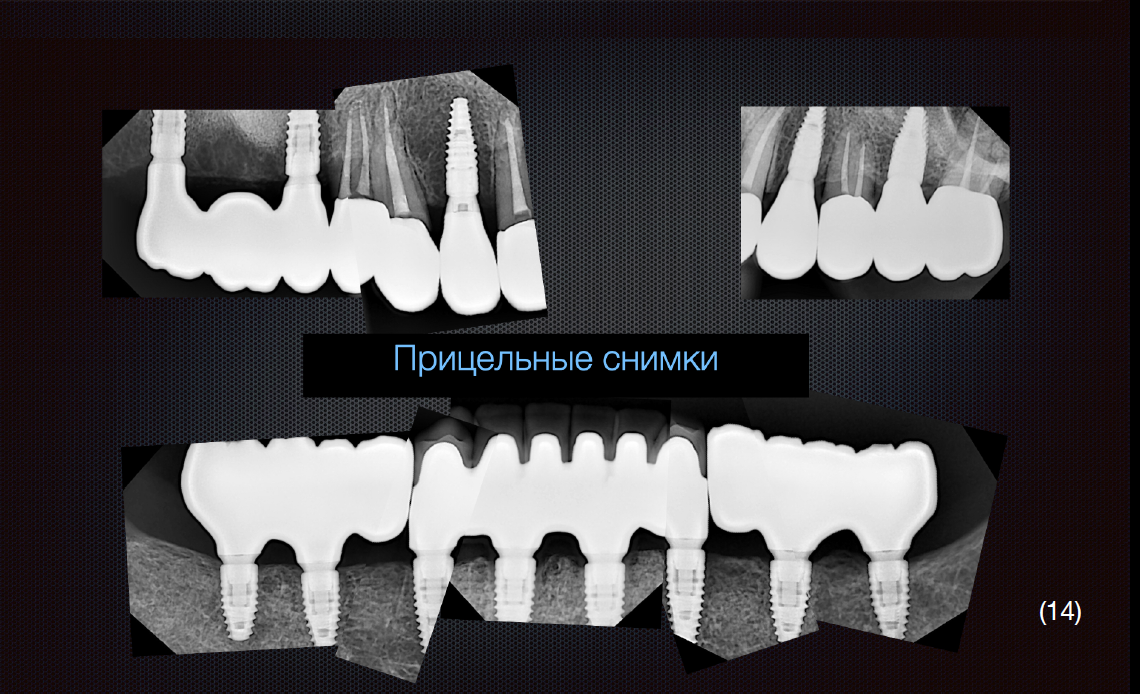

Протезування проводилось з використанням цифрового протоколу.

На нижню щелепу було виготовлено роздільну конструкцію. В бічних ділянках – мостоподібні протези на гвинтовій фіксації з рівня імплантату.

У фронтальній ділянці комбінована конструкція – каркас із діоксиду цирконію, фіксований до імплантатів гвинтами, на який цементуються коронки із прес-кераміки. Такий тип конструкції вибрано через високу надійність та прогнозованість в довготривалій перспективі, що підтверджується даними клінічних досліджень, а також легкість в обслуговуванні.

Верхню щелепу реабілітовано коронками з опорою на зуби та імплантати.